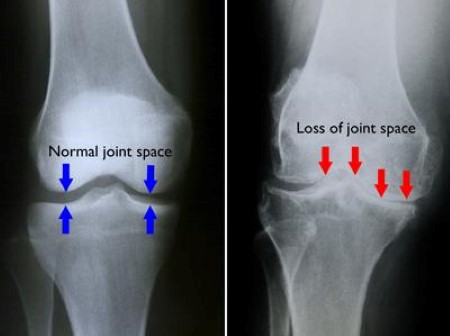

• X-rays. These imaging tests provide detailed pictures of dense structures, such as bone. They can help distinguish between various forms of arthritis. X-rays of an arthritic knee may show a narrowing of the joint space, changes in the bone, and the formation of bone spurs (osteophytes).

normal joint space and loss of joint space

(Left) In this X-ray of a normal knee, the space between the bones indicates healthy cartilage (arrows). (Right) This X-ray of an arthritic knee shows severe loss of joint space.

Images courtesy of Stuart J. Fischer, MD, FAAOS